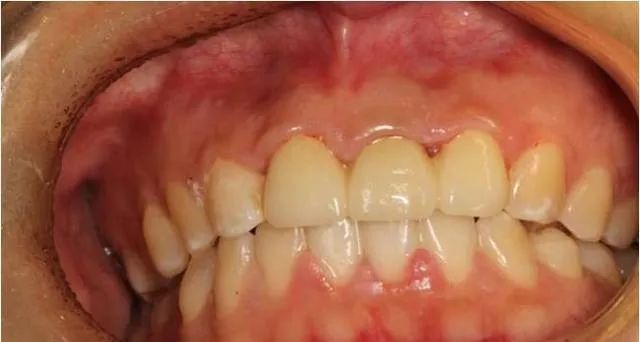

固定修复后口内像

修复前后对比图